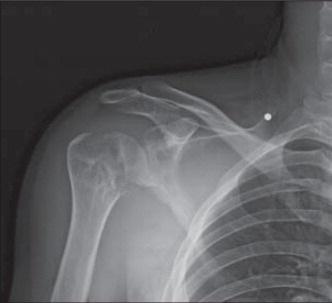

Диагностика

Для выявления патологии врач назначает ряд диагностических процедур:

- Осмотр у травматолога.

- Ультразвуковое исследование или рентгенография.

- Компьютерная томография или магнитно-резонансная томография.

- Проведение артроскопии.

- Лабораторные анализы крови и мочи.

- В некоторых случаях может потребоваться забор жидкости из плечевого сустава, лечение будет определено на основе полученных результатов анализов.